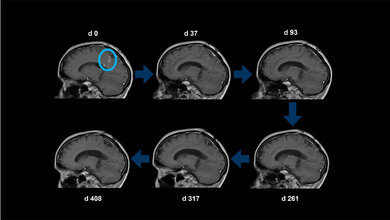

Bei keinem der Geimpften beobachteten die Ärztinnen und Ärzte schwerwiegende Nebenwirkungen. Fünf der acht behandelten Patienten entwickelten spezifische Immunantworten gegen das mutierte Protein, dabei stand die Aktivierung von CD4-T-Helferzellen im Vordergrund. Bei einer der Betroffenen, die eine starke Immunreaktion gezeigt hatte, bildete sich der Tumor komplett zurück, sie blieb für 31 Monate tumorfrei.